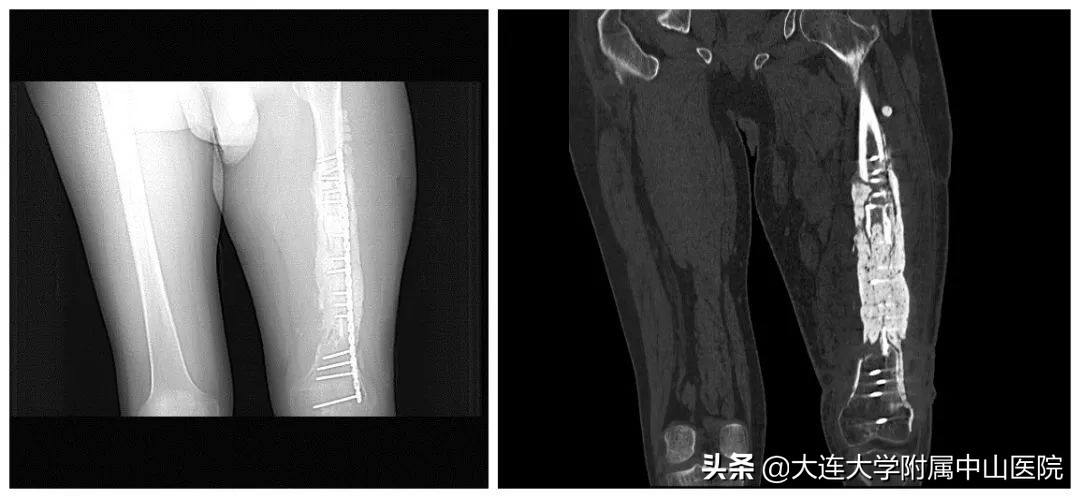

就在患者要放弃治疗,准备截肢的时候,偶然得知大连大学附属中山医院造船分部擅长于骨创治疗,就抱着试试看的态度来到了造船分部。接诊的秦松主任与患者做了深入沟通,打消了患者的悲观情绪,为患者制定了详尽的手术方案,在患者的积极配合与秦主任团队的共同努力下,前后历时一年,经过了病灶清除术、抗生素骨水泥占位术、腓骨移植术等数次前卫医疗技术手段,通过传统及现代治疗技术相结合,不仅控制住感染,还将长达18厘米长的骨缺损全部修复,患者终于保住了大腿,又重新站立起来了,回归了正常生活。